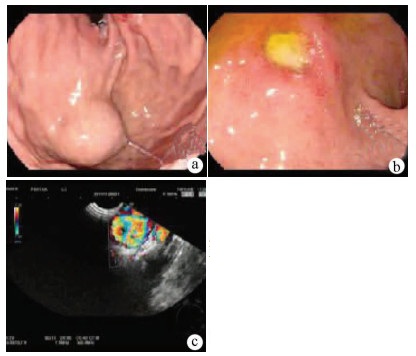

Expert consensus on the imaging diagnosis of hepatic echinococcosis

Radiology of Infection Sub-branch, Radiology Branch, Chinese Medical Association, Committee on Radiology of Infectious, Radiology Branch, Chinese Medical Doctor Association

2021, 37(4): 792-797. DOI: 10.3969/j.issn.1001-5256.2021.04.014

Abstract(1244) HTML (604) PDF (2065KB)(121)

Abstract:

Echinococcosis is a zoonotic disease with global distribution and has become an issue seriously affecting public health around the world. Imaging technology plays an important role in the early diagnosis, preoperative evaluation, and treatment outcome monitoring of hepatic echinococcosis. At present, no consensus has been reached on the imaging diagnosis of echinococcosis, which brings difficulties in the learning and training of imaging professionals and the standard diagnosis and treatment of echinococcosis in clinical practice. For this reason, Beijing YouAn Hospital, Capital Medical University, and The First Affiliated Hospital of Xinjiang Medical University organized the radiologists engaged in infection and inflammation from several hospitals to reach a consensus on the basis, principles, and criteria for the imaging diagnosis of echinococcosis and the differential diagnosis of echinococcosis, with reference to international guidelines, related articles, the latest research findings in China and globally, and the methodological requirements for the establishment of guidelines and standards in evidence-based medicine, so as to provide a clear diagnostic basis for clinicians in the clinical application of hepatic echinococcosis imaging.